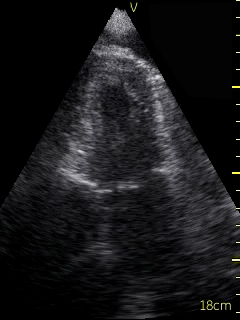

Video 1 (online supplement; Figure 1) demonstrates a parasternal long axis view with the pericardial effusion noted to be posterior to the left ventricle in this view. Video 2 (online supplement; Figure 2) is a short axis view of the heart which is showing that the effusion is surrounding the heart. Video 3 and 4 (online supplements; Figures 3 & 4) demonstrates that the pericardial effusion is present significantly surrounding the apex as well. An echocardiogram confirmed the POCUS findings and cardiology was consulted to conduct a pericardiocentesis, following which the patient’s symptoms resolved. The effusion was thought to be chronic and transudative. In this case, the use of POCUS at the bedside allowed for rapid detection of a large pericardial effusion and subsequent treatment.